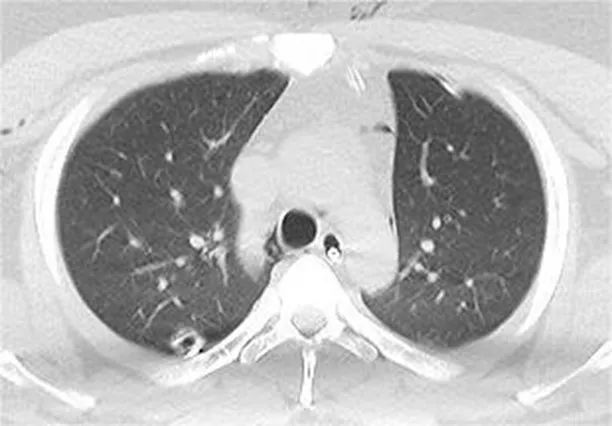

待小明生命体征稳定后开始手术,麻醉医生通过间断性停呼吸、小潮气量通气,协助胸外科医生暴露右侧胸腔手术视野,打开双侧纵隔胸膜、切除双侧纵隔脂肪组织,打通了胸部的三个空间(左侧胸腔、纵隔及右侧胸腔),快速减压,仅用30分就顺利完成手术。在我院ICU刘娇主任医护团队保驾护航下,小明很快拔除气管插管,转入胸外科普通病房,经过康复科和护理团队术后的指导康复锻炼,小明在6天后顺利康复出院。

术后复查CT显示纵隔气肿基本吸收